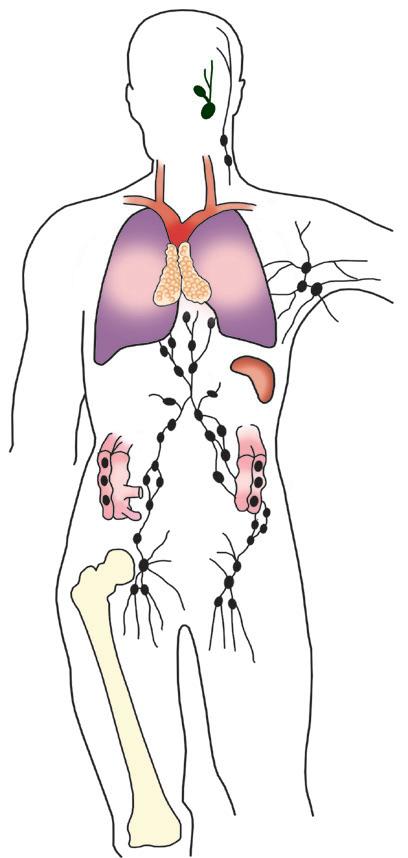

вий мозок, тимус) і

Організм людини, як і інших живих істот, має захисні механізми, що захищають від вірусів, хвороботворних бактерій, паразитичних грибів і тварин, шкідливих речовин, токсинів та канцерогенів, звільняє від перероджених власних клітин. Імунна регуляція забезпечується багатьма системами організму, наприклад, шкіра, дихальна система, травна система, ендокринна система, система крові.

Антигени — це чужорідні білкові речовини, які при потраплянні в

білка перфорину знищує його. Інша

ж частина продовжує циркулювати з кров’ю. У разі повторного контакту з таким самим антигеном вони дають велику кількість Т-лімфоцитів, які й знищують антиген. Основними властивостями антигенів є: генетична відмінність (чужорідність), імуногенність (здатність викликати імунну відповідь) та специфічність. За джерелом надходження антигени поділяють на зовнішні (віруси, бактерії) та внутрішні (пухлинні клітини, вірусні білки). В-лімфоцити, що утворюються в кістковому мозку, виробляють антитіла. Антитіла — це білкові речовини, синтезовані організмом у відповідь на чужорідні білки. Усі антитіла людини — це імуноглобуліни плазми крові, які забезпечують захист, зв’язуючи антигени. При першому контакті В-лімфоцита з антигеном здійснюється «запам’ятовування» антигена і поділ клітин. Більша частина утворених В-лімфоцитів осідає в лімфоїдній системі організму і перетворюється на плазмоцити, які продукують антитіла. Решта В-лімфоцитів виходять у кров і стають В-лімфоцитами імунологічної пам’яті.

Які функції біологічних бар’єрів в організмі людини?

Біологічні бар’єри — здатність організму за допомогою особливих фізіологічних механізмів